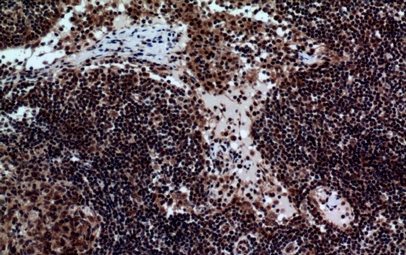

(Immunohistochemistry of paraffin-embedded Human lymph nodes tissue using NKp44 Polyclonal Antibody at dilution of 1:100.)